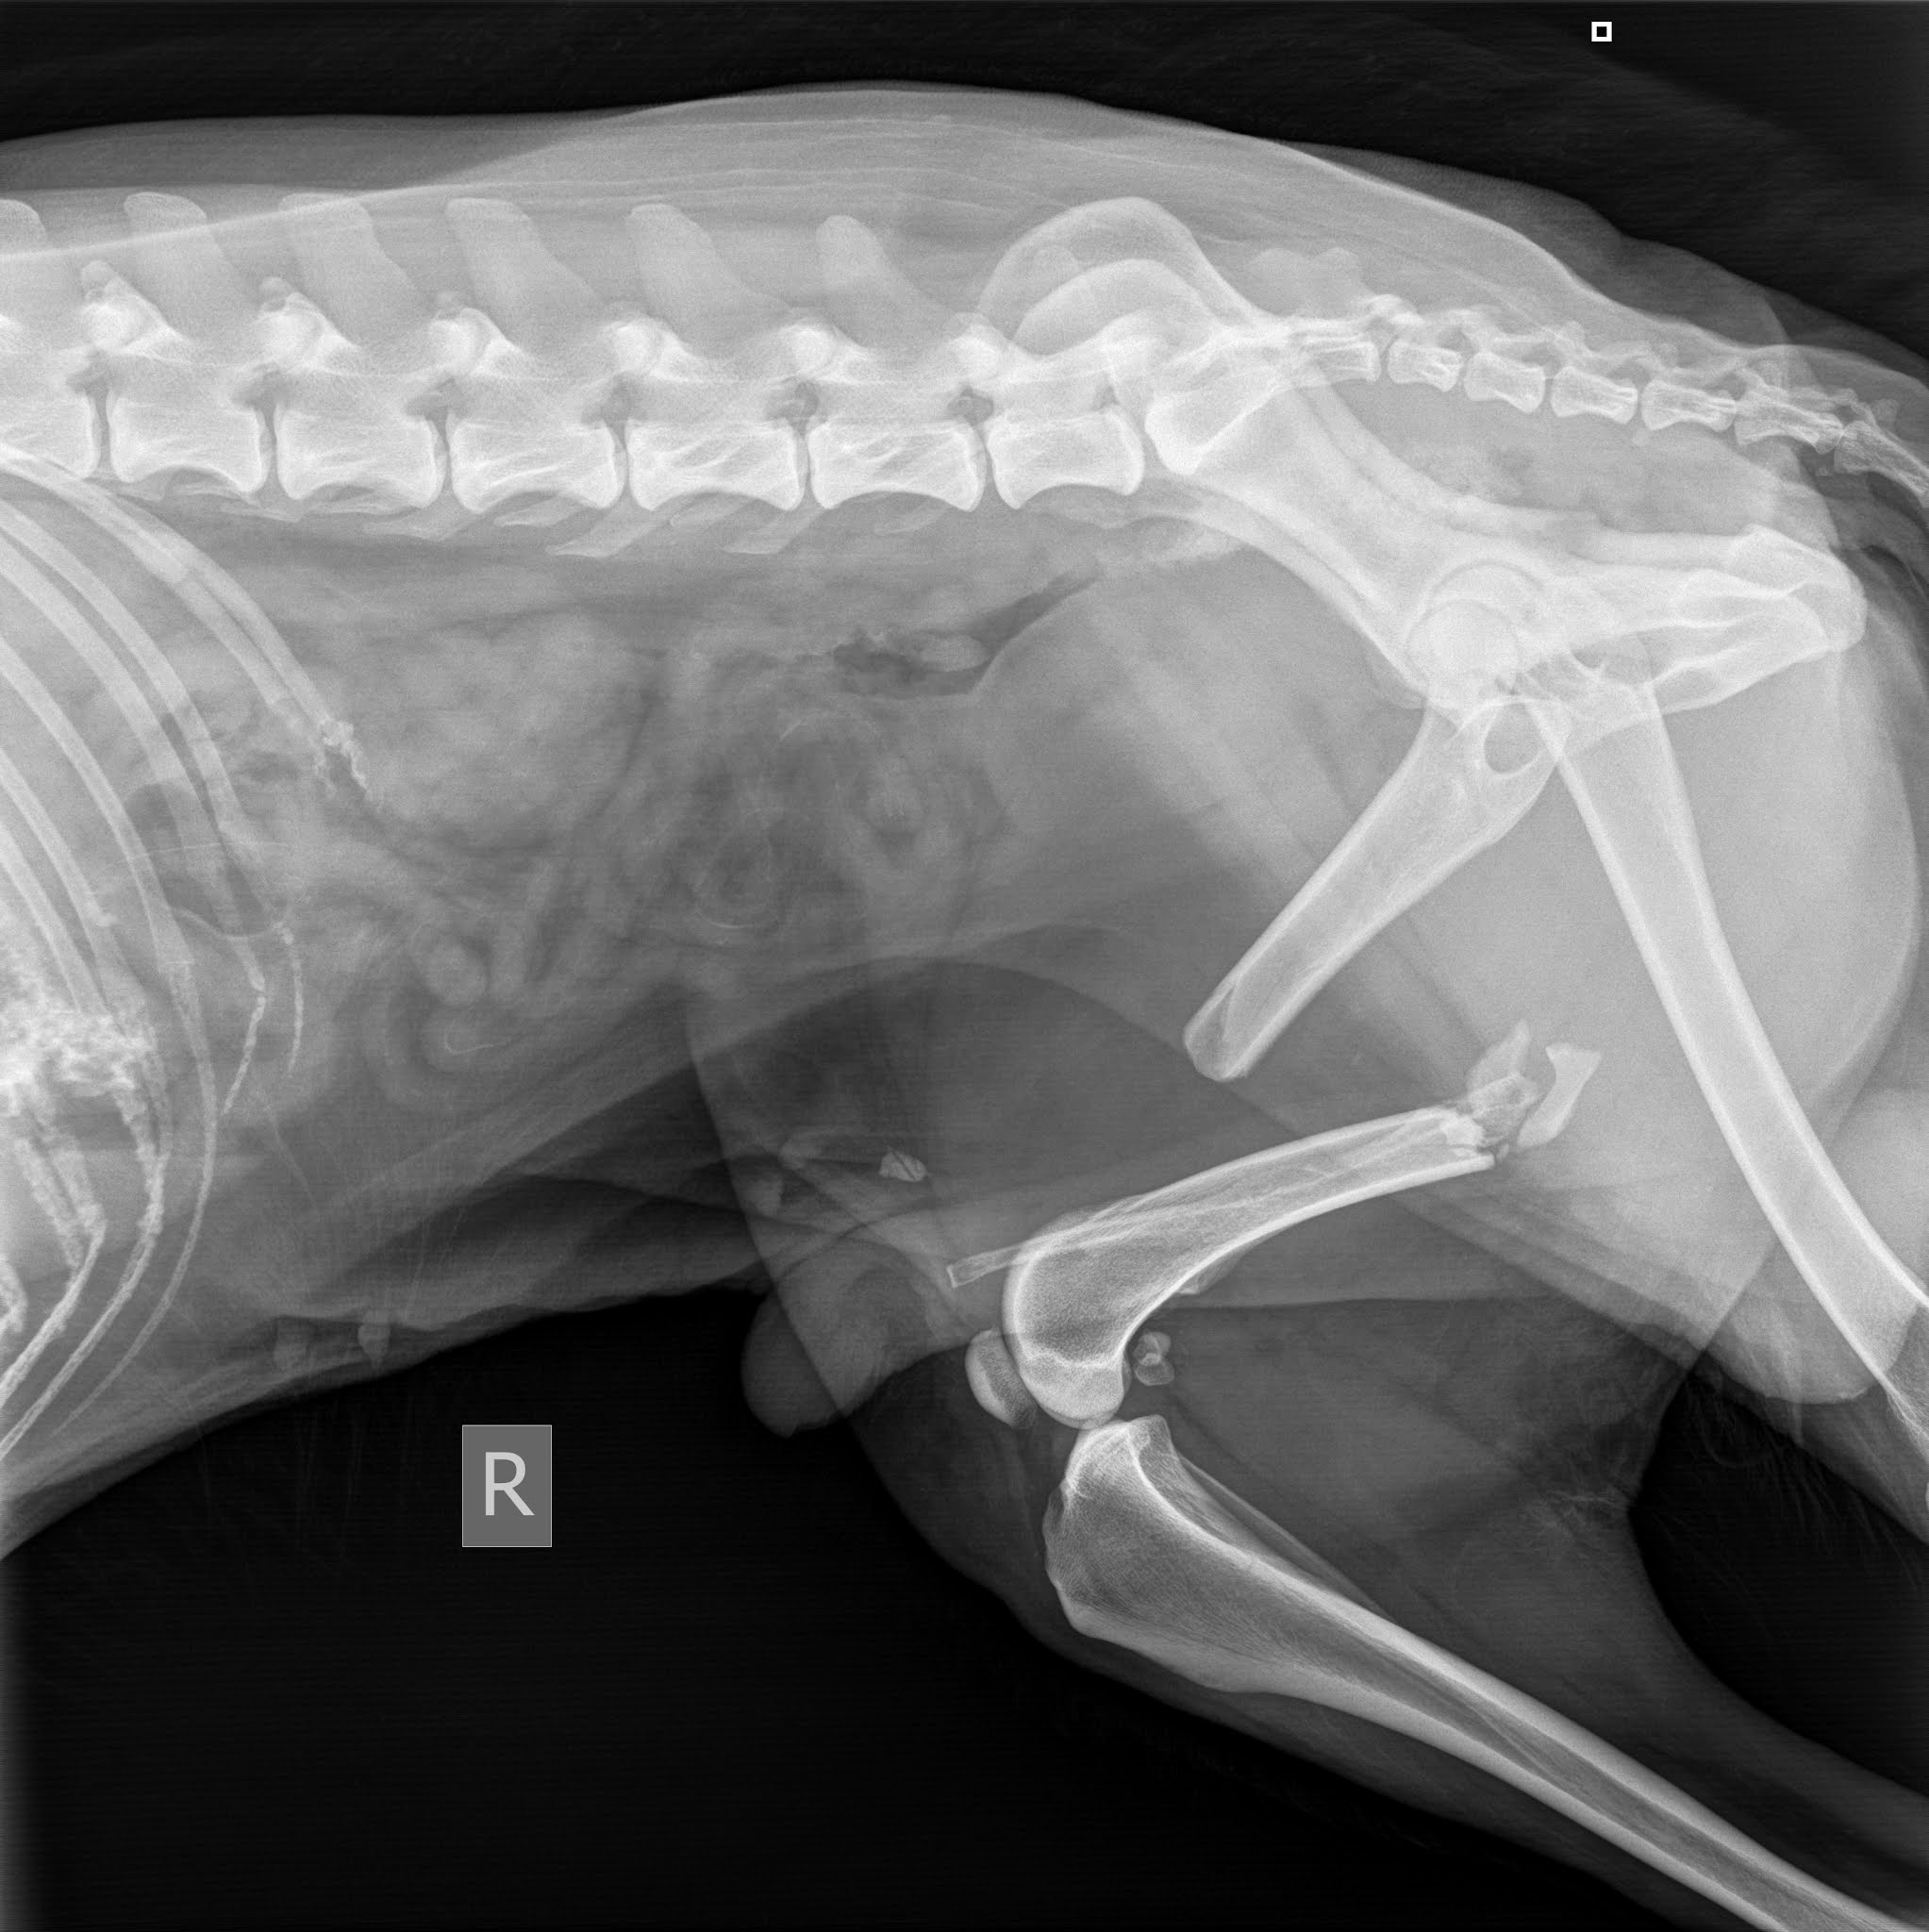

Signe põrutas ettenäidatud talusse ja seal valitsev olukord ning kõikjal vedelev koerasitt kinnitasid naabrinaise sõnu. Perenaist ennast polnud taas kodus. Ja tühja temaga ning edasi viis tee juba Tartusse Maaülikooli väikeloomakliinikusse. Uuriti-puuriti ja vaadati külmunud koerake üle. Röntgenpilt kinnitas traumat ja reieluu oli pooleks, mis pooleks. Õnneks mitte halva koha pealt ja seda annab lõdvalt lappida. Vaagen oli terve, siseorganid ka, aga täpsema selguse annab juba põhjalikum uuring.